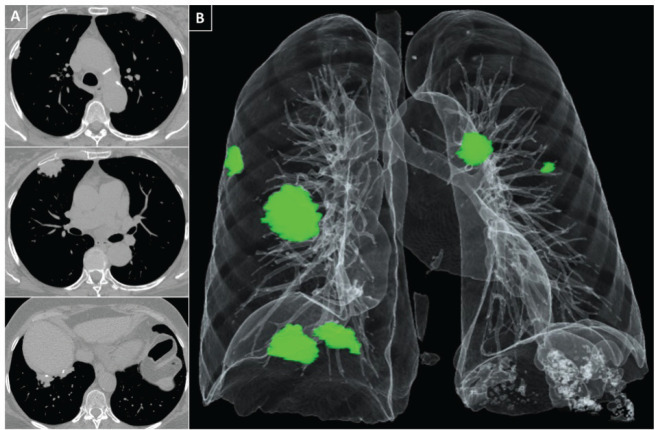

本报告强调了在美发和美容沙龙行业接触石棉的职业健康风险,以一位67岁的美发师和美甲师为例。患者的病史、工作活动和检查结果提示可能与石棉相关的胸膜斑块。职业接触有害化学品,包括滑石粉产品中的石棉,构成严重的健康风险。尽管许多国家都颁布了石棉禁令,但直到2012-2015年,巴西才开始大量使用石棉,并于2023年全面禁止使用石棉。本报告强调需要持续讨论石棉检测和严格执行禁令,同时确保不含石棉的滑石粉,以保护美容行业工人的健康。

This report highlights the occupational health risk of asbestos exposure in the hair and beauty salon industry, exemplified by the case of a 67-year-old hairdresser and manicurist. The patient's medical history, work activities, and examination findings indicated potential asbestos-related pleural plaques. Occupational exposure to harmful chemicals, including asbestos in talc products, poses serious health risks. Despite asbestos bans in many countries, Brazil experienced extensive asbestos usage until 2012-2015, with a complete ban taking effect in 2023. This report emphasizes the need for ongoing discussions on asbestos detection and strict enforcement of bans, while ensuring asbestos-free talcum powders to protect the health of beauty industry workers.